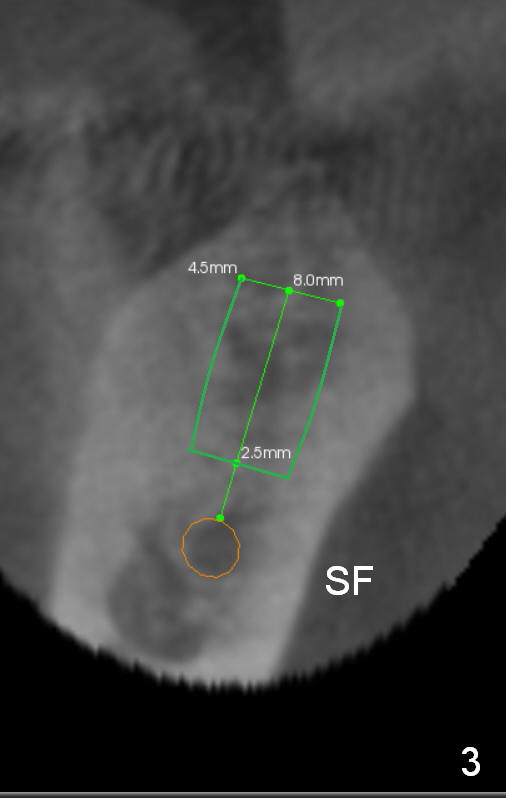

Before crown removal, use the 3.5 mm (vs. normally 5 mm) implant spacer and #15 to mark an entrance point for #31 implant (make a cross over the crestal gingiva).  After crown removal, insert a 3 mm Guide Pin into #30 implant well as a parallel pin.  Use 2 mm pilot drill to start osteotomy through the cross and then make incision.  While drilling and reaming, pay attention to the submandibular fossa (Fig.3 SF) and the Inferior Alveolar Canal (orange).  When a 4.5x8 mm implant is placed, place abutments and make splinted provisional.